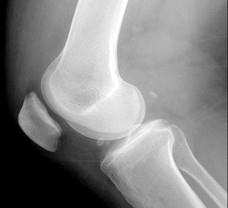

问题 女,65岁,右膝痛,活动受限,请结合图像,选出最可能的诊断 ( )

选项 A、类风湿关节炎 B、痛风 C、创伤性关节炎 D、退行性骨关节病 E、神经性关节病

答案 D